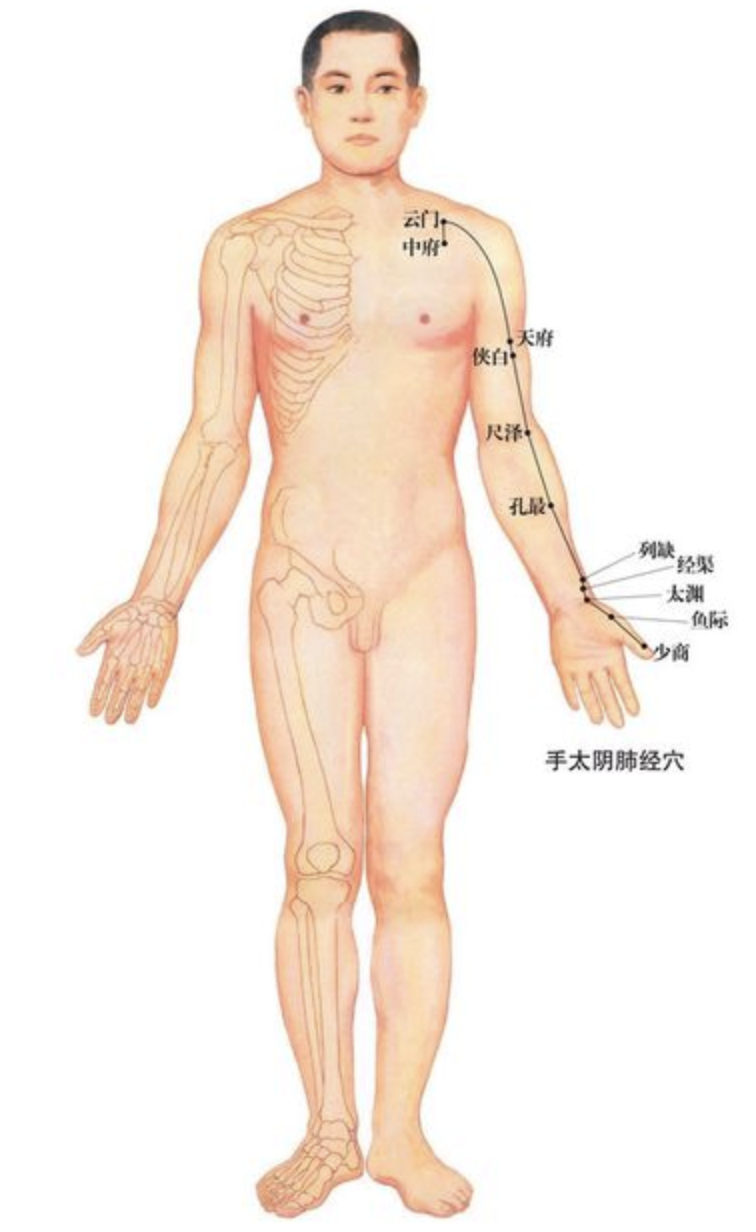

【(一)手太阴肺经(图10-19-1)】

图 10-19-1 手太阴肺经循行及常用腧穴

1、时辰 寅时 3 ~ 5

2、歌诀 手太阴肺十一穴,中府云门天府列,次则侠白下尺泽,又次孔最与列缺,经渠太渊下鱼际,抵指少商如韭叶。

3、经脉循行 肺手太阴之脉,起于中焦,下络大肠,还循胃口,上膈属肺,从肺系横出腋下,下循臑(nào)内,行少阴心主之前,下肘中,循臂内上骨下廉,入寸口,上鱼,循鱼际,出大指之端;其支者,从腕后直出次指内廉,出其端。

即该经起自中焦,向下联络大肠,回过来沿着胃的上口贯穿膈肌,入属肺脏,从肺系(气管、喉咙)横行出胸壁外上方(中府),走向腋下,沿上臂前外侧,行于手少阴心经和手厥阴心包经的外面,至肘中(尺泽)后再沿前臂桡侧下行至寸口(桡动脉搏动处),又沿大鱼际外缘出拇指桡侧端(少商)。

其支脉从腕后桡骨茎突上方(列缺)分出,经手背虎口部至食指桡侧端(商阳)。脉气由此与手阳明大肠经相接。